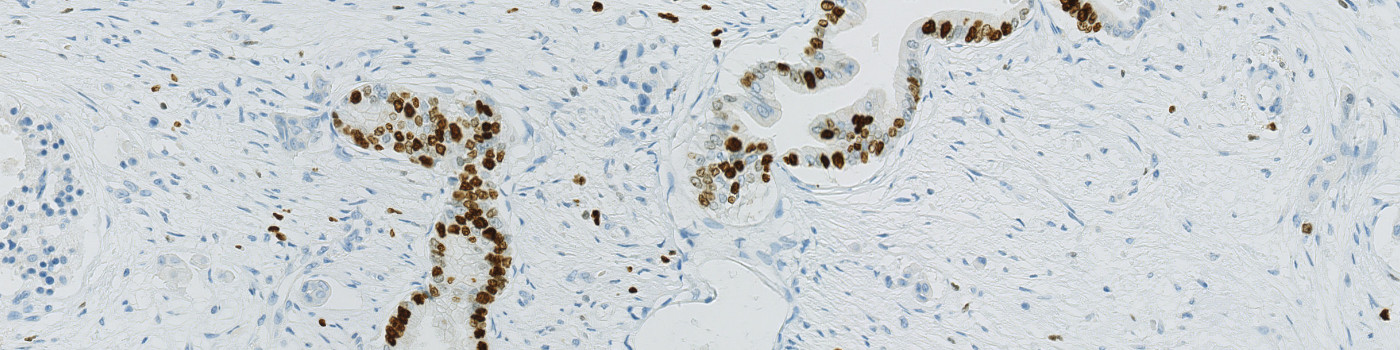

The Ki-67 protein is associated with cellular proliferation, and the protein is present in the nucleus of all cells that are in the active phase of the cell cycle, but absent in resting cells, see [1]. The cell proliferation rate can be assessed by Ki-67-immunohistochemical (IHC) staining, and this can be correlated to the tumor grade and the clinical course. Ki-67 proliferative index is suggested to be an important prognostic variable and is used as a grading parameter for neuroendocrine neoplasms, see [2], including pancreatic neoplasms.

This APP can be used to assess tumors by determining the Ki-67 positivity. The protocol detects and classifies nuclei as positive or negative and returns an average proliferation index for the entire tumor region. Tumor regions must be identified and outlined manually within a region of interest (ROI).

The APP works within an automatically or manually outlined tumor region of interest (ROI). Within each ROI, nuclei are detected and classified into Ki-67 positive or negative. The first image processing step involves a segmentation of all nuclei in the ROI. The HDAB-DAB color deconvolution band is used to detect positively stained nuclei and a multiplication of the red and blue color band is used to detect negative nuclei. A method for nucleus separation which is based on shape, size and nuclei probability is used, employing a fully automated watershed-based nucleus segmentation technique. As a post-processing step, nuclei areas that are too small are removed. The image obtained after post-processing is used to determine the output variables.